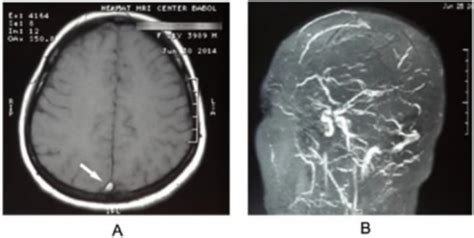

After the scan is complete, a neuroradiologist—a doctor who specializes in brain imaging—will analyze the images. They will look for signs of blood clots, narrowed vessels (stenosis), or malformations that could be disrupting normal circulation. Your primary physician will receive a formal report and will schedule a follow-up appointment to discuss these findings with you in detail and determine the appropriate path forward for treatment if necessary.